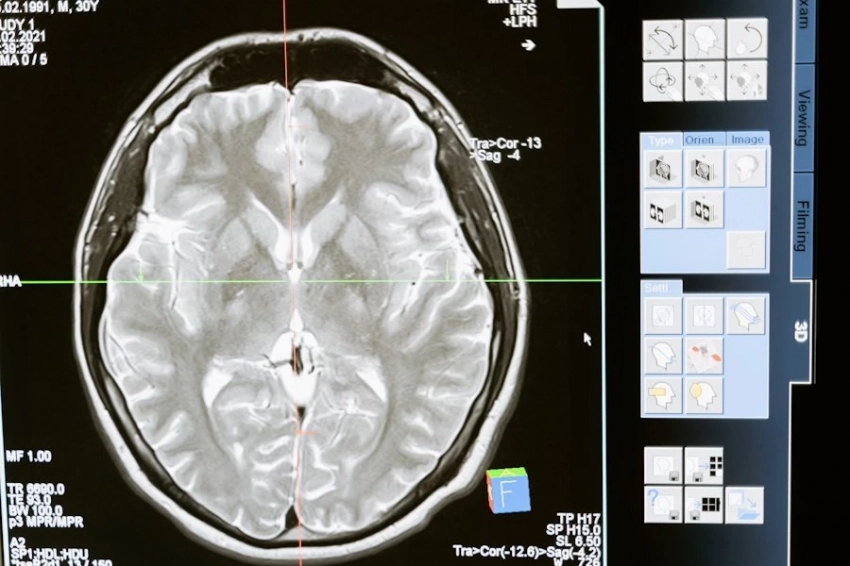

Фото из открытых источников Старческая деменция — это заболевание, при котором у человека постепенно нарушаются память, способность к логическому мышлению и концентрации внимания. В итоге когнитивные функции существенно снижаются, а личность претерпевает значительные изменения. Японские ученые обратили...